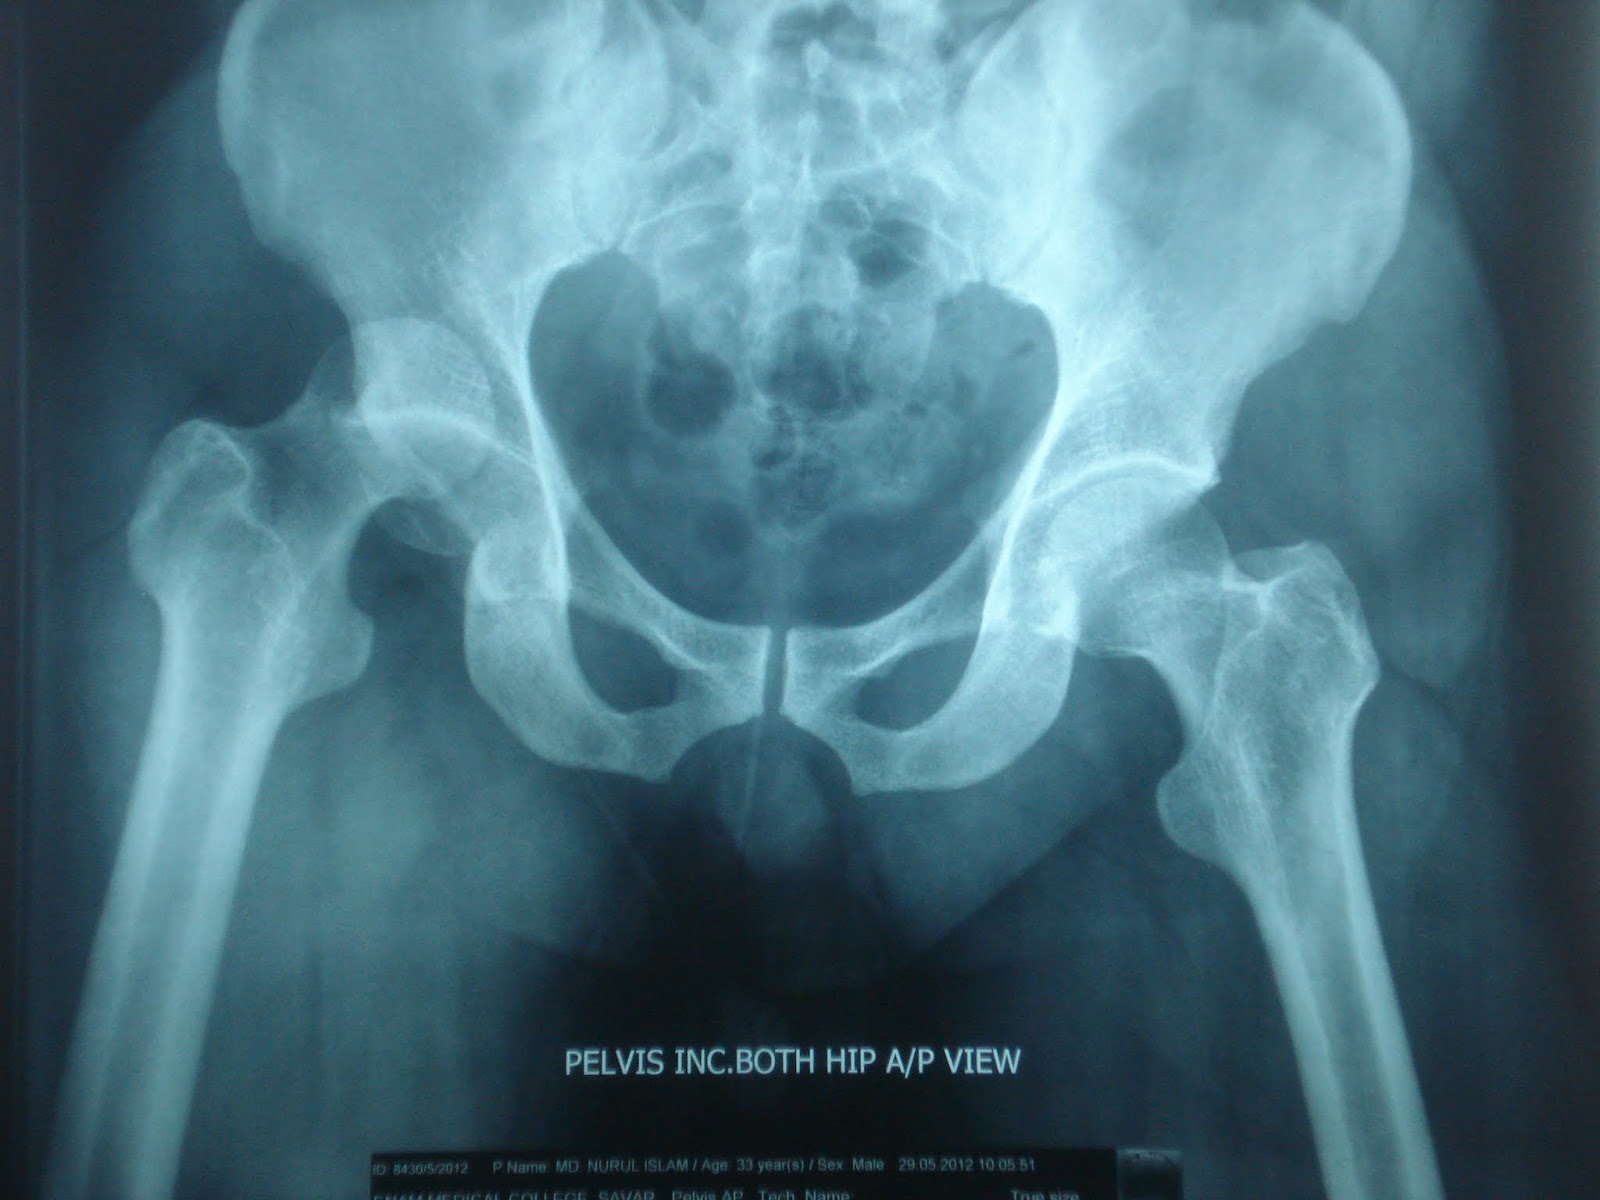

Right hip femoral neck fracture diagnosis code? In the vast majority of cases, a hip fracture is a fragility. Women experience 80% of hip fractures, and the average patients with hip fractures have pain in the groin and are unable to bear weight on the affected extremity. Left hip fracture icd 9. V54.13 aftercare for healing traumatic fracture of hip. Hip fractures are cracks or breaks in the top of the thigh bone (femur) close to the hip joint. V13.51, v13.52, and v15.51 can all be used depending on the cause of the fracture. It fits directly on the end of the lever and has a hole that lines up with the one in the end of the lever. You can always come back for left hip fracture icd code because we update all the latest coupons and special deals weekly. Hip compression fracture healing time. During the physical examination, displaced. Unsp fracture of left femur, init encntr for closed fracture; A patient has osteoarthritis in the left hip joint due to osteoporosis. Strn and dislocation except femur, hip, pelvis and thigh with. It covers icd codes 800 to 999. Type ii odontoid fracture icd 9 code. Revise new code new code new code new code.